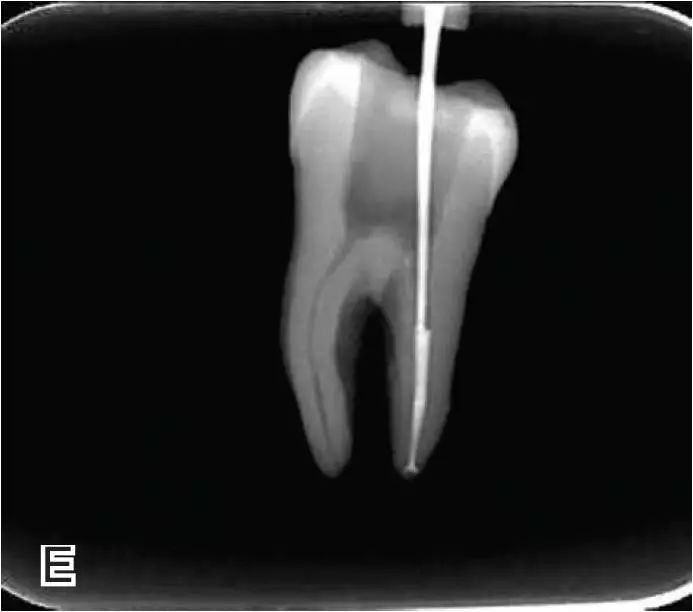

热牙胶根中上段的充填

在完成根尖段的充填后,使用热塑牙胶注射仪对根管中上段进行分层充填,一般分2~3次完成充填,每次充填均使用相应直径大小的垂直加压器进行加压。拍片确认充填效果。